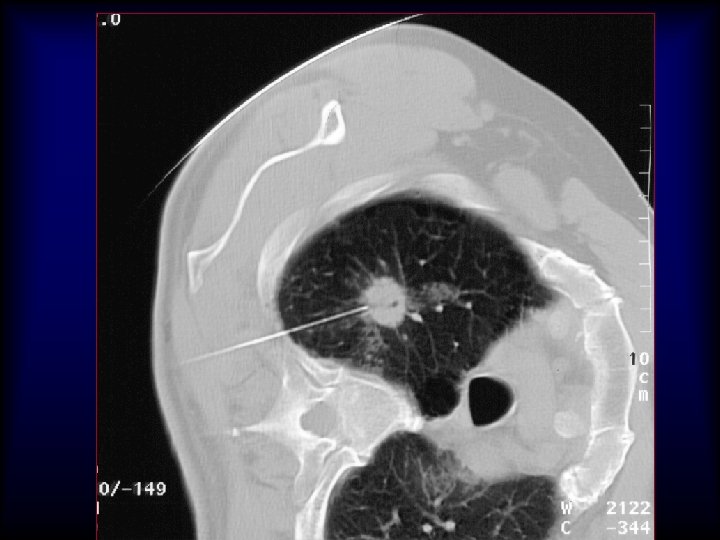

20 G/9 cm/10 T x 25 x 40 x 200 5 mm Adenocarcinoma H&E